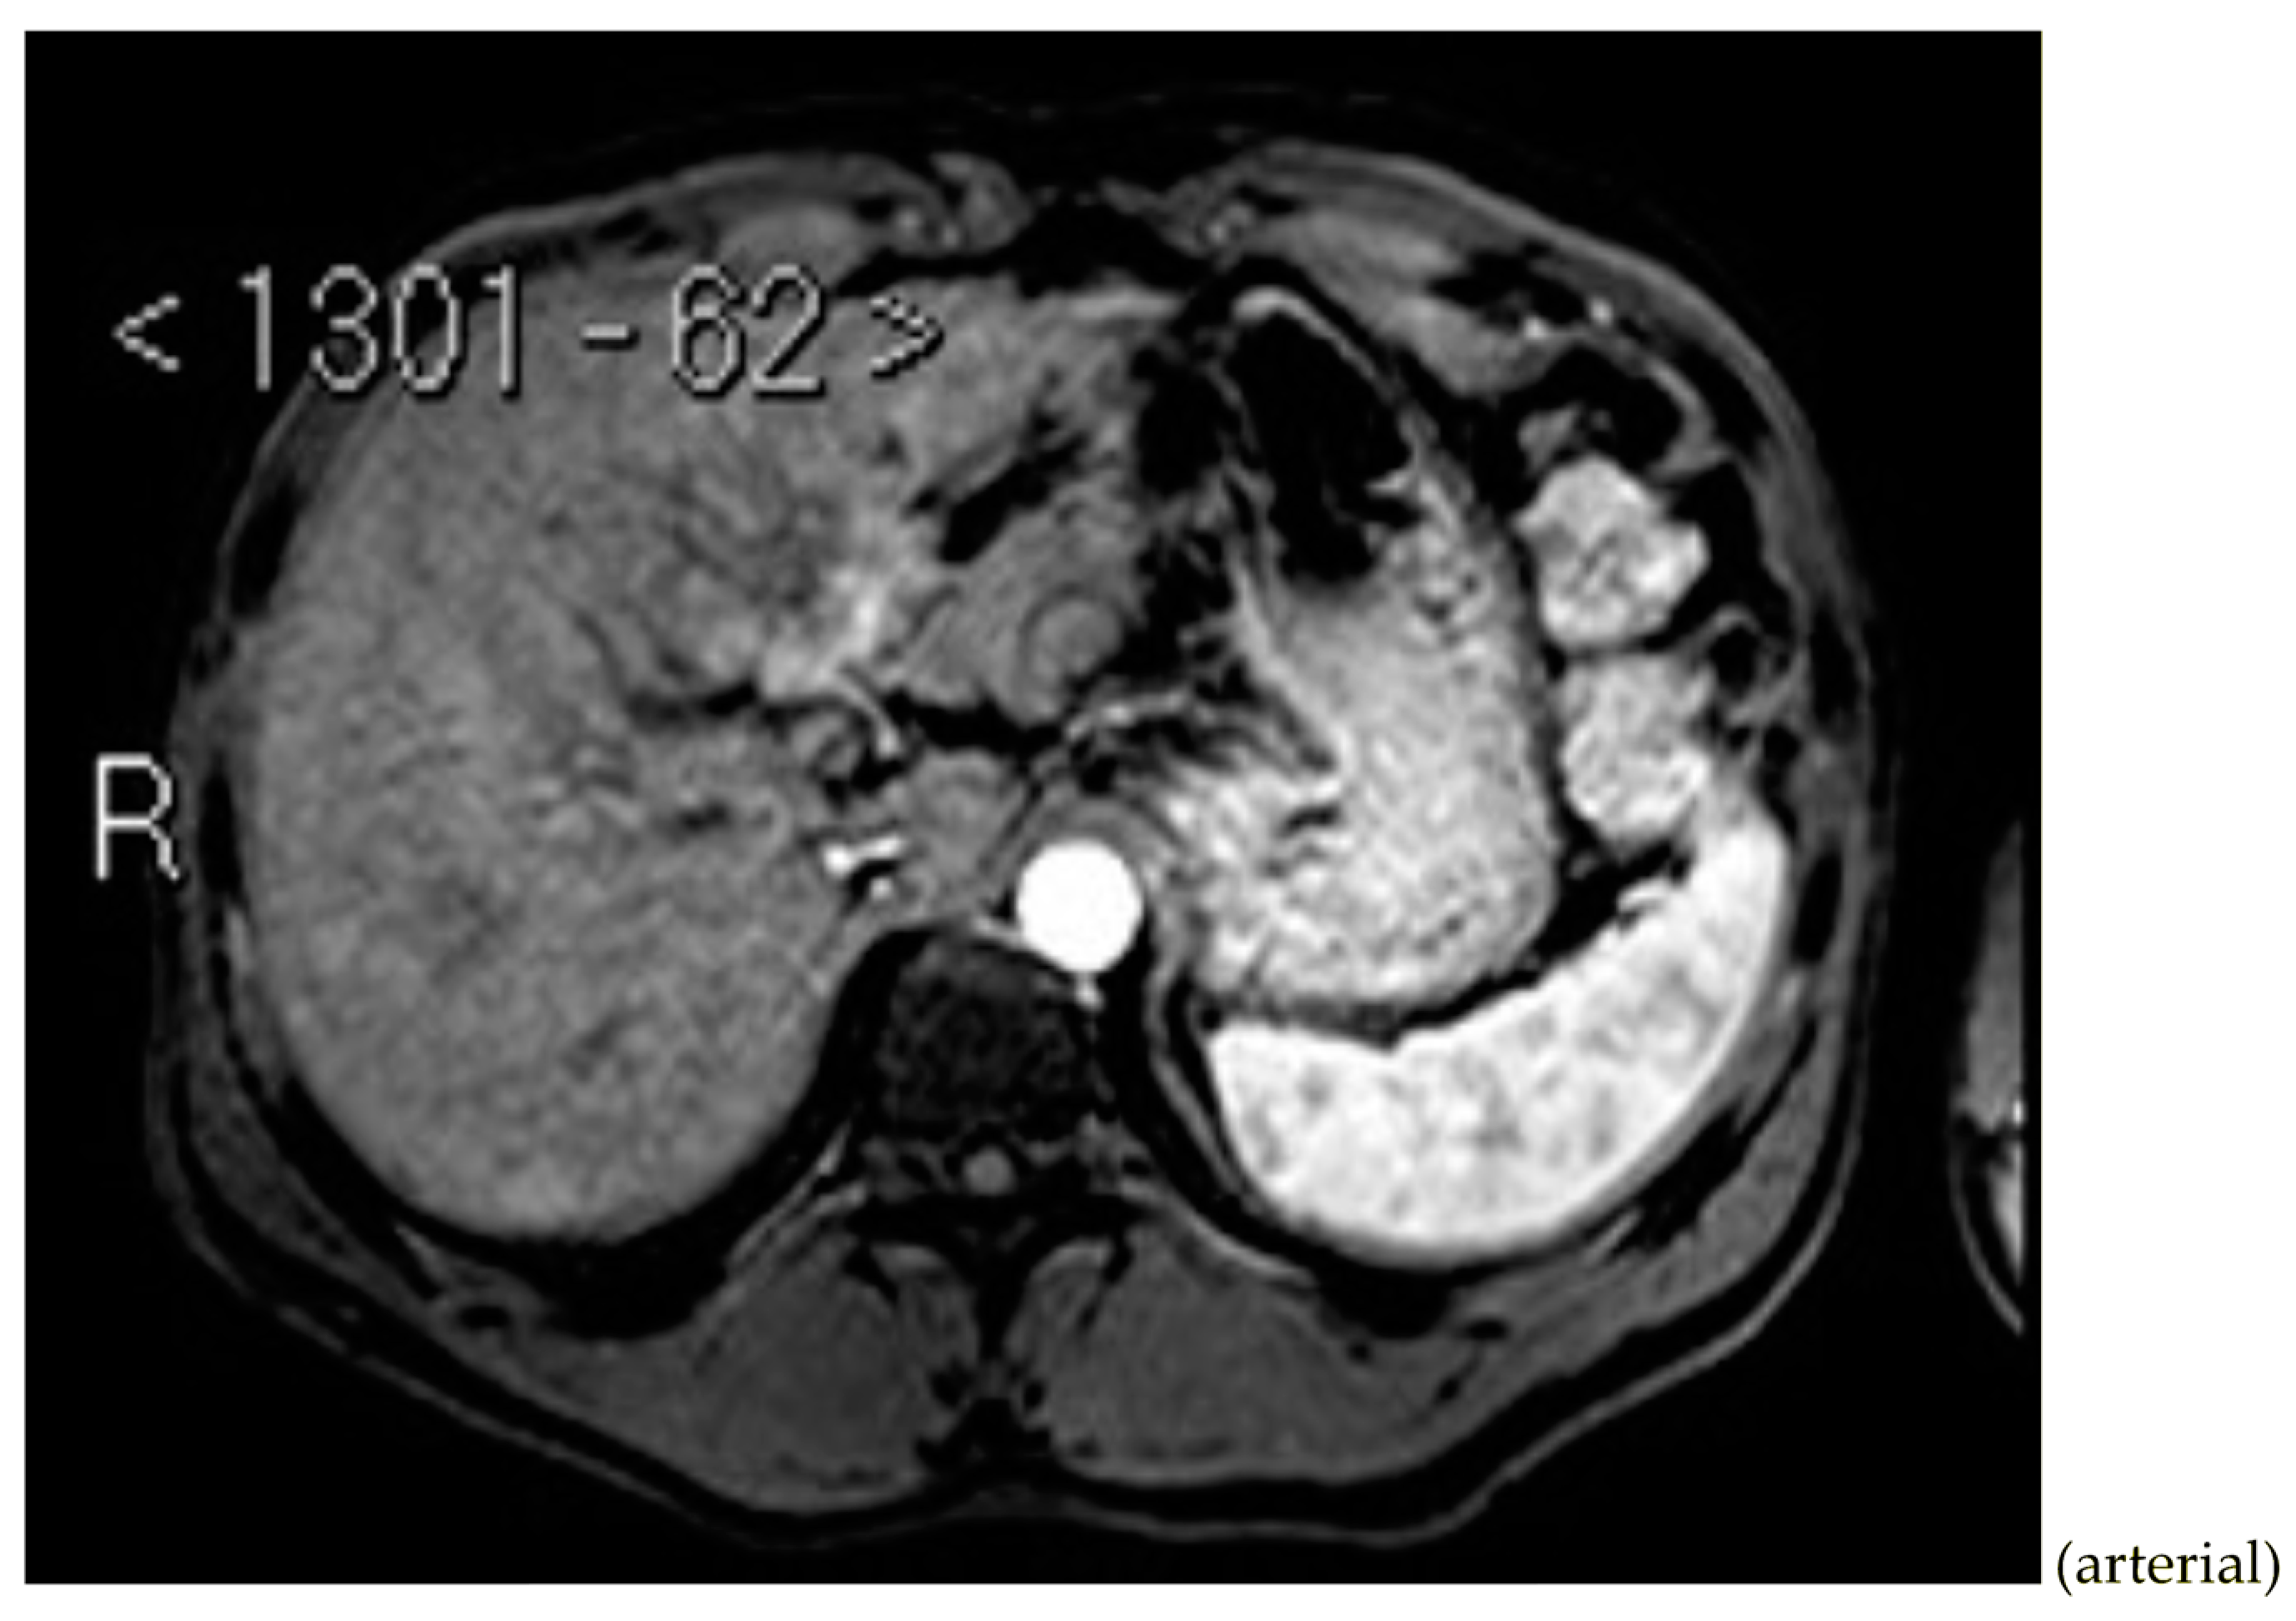

Subsequently, an upper-abdomen Computed Tomography (CT) scan and liver Magnetic Resonance Imaging (MRI) were performed (Figure 1, Figure 2, Figure 3, Figure 4, Figure 5, Figure 6 and Figure 7).

Figure 5.

MRI T2.

A mass of 1.8 cm was detected within the biliary branch for the third hepatic segment, characterized by nodular impregnation in the arterial phase and irregular and partial washout in the portal venous phase. These findings were compatible with a heterologous lesion, although it was not possible to perform a diagnosis among HCC, intrahepatic CCA or other pathological lesions.

HCC typically has an increased arterial blood supply, so it usually shows hyperattenuation in the arterial phase and hypoattenuation in the portal venous phase, compared to the hepatic parenchyma.

Most HBDTTs should show the same enhancement pattern. However, some HCCs can show iso- or hypoattenuation in the arterial phase, with the enhancement in the arterial phase inversely correlated with the degree of blood clots and necrosis. So, hypoattenuation in the portal venous phase seems to be the most important imaging feature to distinguish HCC with BDTT from perihilar CCA [17].

Washout in the portal venous phase is also the main feature to distinguish HCC with BDTT from intrahepatic CCA, together with the presence of tortuous tumoral vessels [17].

In conclusion, the diagnosis of HCC with BDTT can be reasonably considered in the presence of lesions of both hepatic parenchyma and bile ducts with a cirrhotic underlined liver disease, especially if they show typical washout in the portal venous phase.